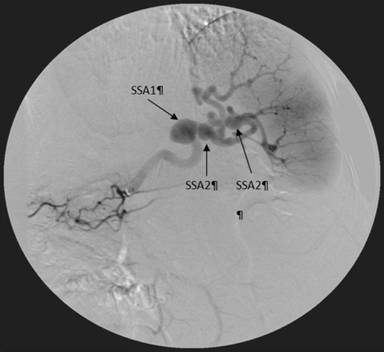

One day after admission, the occurrence of hematemesis urged repeated endoscopy, which revealed the fresh blood originating from the papilla of Vater (Figure 1). Endoscopic retrograde cholangiopancreatography was performed, demonstrating patent pancreatic duct and blind remnant of native common bile duct without communications between pancreaticobiliary tract and blood vessels. During the procedure few blood clots originated from the papilla of Vater. Multislice contrast computed tomography showed moderate enlargement of the pancreatic head with suspected hematoma (Figure 2), along with three splenic artery aneurysms, of 30 mm, 12 mm and 8 mm in diameter, in the distal arterial segment, as well as anastomotic stenosis of native and donor hepatic artery. However, contrast extravasation on visceral angiography was not detected (Figure 3). The embolization of the splenic artery aneurysms was judged unfeasible due to tortuosity of the splenic artery, wide neck of the major aneurysm and proximity of other two aneurysms to the splenic hilum. Supportive therapy stabilized the patient and gastrointestinal bleeding resolved. The patient was scheduled for surgery; however, subsequent development of hepatic artery thrombosis, resulted in multiple liver abscesses and septic episodes (Figure 4). On several occasions Enterococcus faecium and Klebsiella pneumoniae were identified from abscesses and blood cultures. Despite of a broad-spectrum antibiotic therapy and percutaneous drainage the fever persisted, although gastrointestinal bleeding did not reoccur. Three months later, the patient underwent liver re-transplantation and splenectomy. During the three past years of follow-up, the patient has remained uneventful.

Figure 3. Angiography of the splenic artery showing three splenic artery aneurysms (SAAs), of 30 mm (SSA1), 12 mm (SSA2) and 8 mm (SSA3) in diameter, in the distal arterial segment without contrast extravasation. |